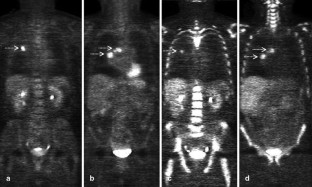

Fig. 3